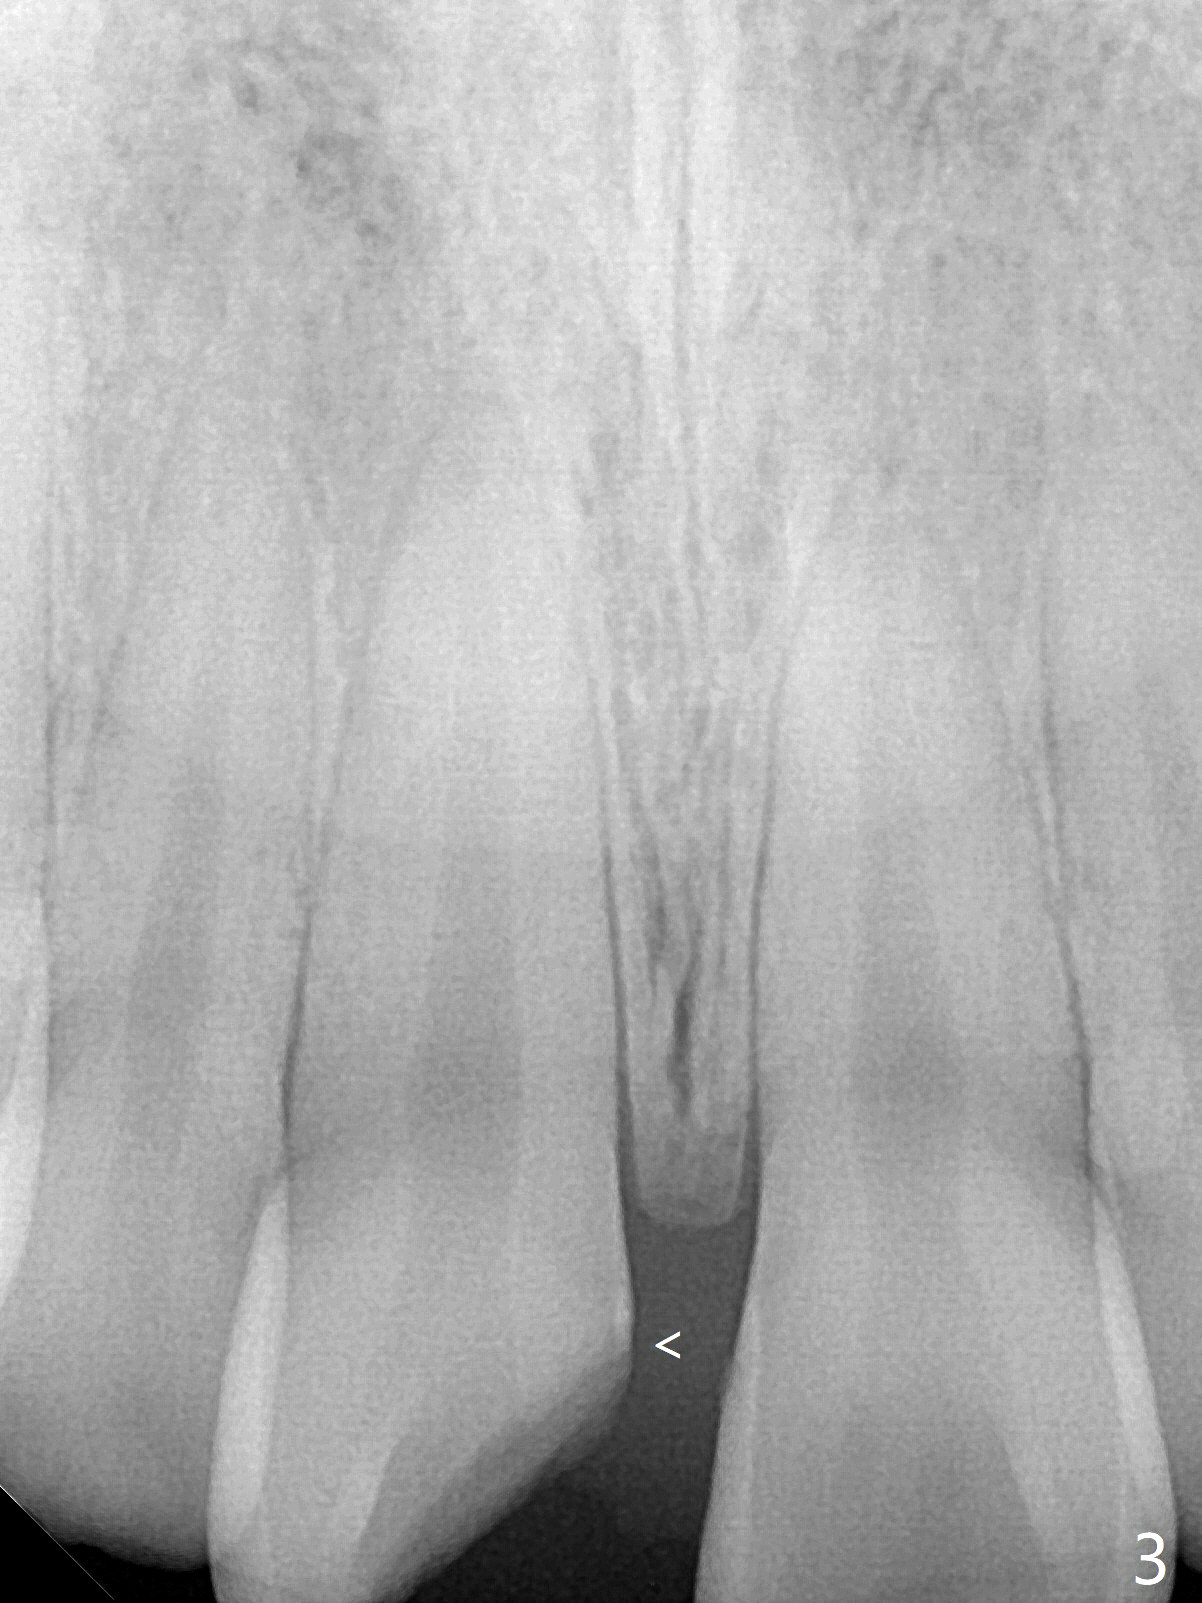

A 16-year-old man fractured the tooth #8 yesterday (Fig.1) with pulpal exposure (Fig.2) and slightly subgingival (Fig.3 <). With 2 gingival retraction cords, rubber dam and floss, the mesial margin is exposed (Fig.4). The mesial pulpal horn is increased slightly with a 330 bur with minimal pulpotomy. MTA is applied (Fig.5 <). A curette is placed over the MTA for hemostasis while it is setting. RelyX Ultimate Adhesive Resin Cement bonding is used to reattach the fracture fragment in place (Fig.6,7). Pulpal vitality will be monitored. A crown will be placed if the tooth discolors due to MTA and the pulp remains vital. Mineral trioxide aggregate (MTA), composed mainly of tricalcic silicate, tricalcic alluminate, bismuth oxide, is a particular endodontic cement. It is made of hydrophilic fine particles that harden in the presence of dampness or blood. The re-attached tooth remains asymptomatic 9 days postop (Fig.8) when he returns for prophy.

16岁男孩,昨天右上中切牙撞击电脑发生折裂(图一),近中牙髓角暴露(图二),裂缘稍微龈下(图三 <),使用两个牙龈牵拉线,橡皮障和牙线,近中折裂边缘暴露(图四)。你会如何处理?使用330钻头稍微扩大髓角开口,去除少量牙髓,填入微量MTA (图五<),希望形成新的牙本质,关闭开口,维持牙髓活性。出血控制后,应用树脂粘合剂将断片固定于原位(图五,六,七)。术后9天牙齿无症状(图八),病人回来洗牙。